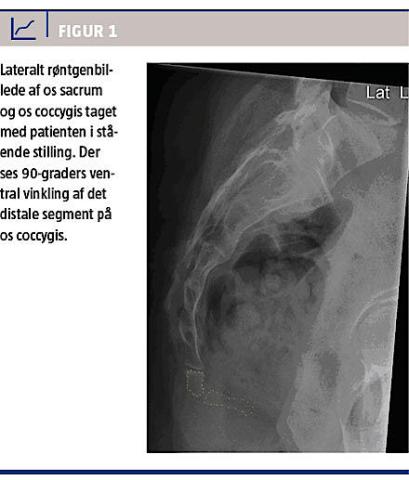

Hun fik i stående stilling taget et røntgenbillede af os sacrum og os coccygis (Figur 1). Røntgenbilledet viste et haleben af normal størrelse og en ventral vinkling på 90 grader af det distale coccygissegment.

Hun var blevet udredt på en abdominalkirurgisk afdeling, hvor undersøgelserne gav mistanke om reduceret tarmlumen pga. kompression af rectum. Ved koloskopi konstaterede man svær passage med initialt upåfaldende slimhinde og ingen tumorer i det stenotiske område af rectum. En MR-skanning af det lille bækken viste ingen tumorer, bløddelsfortykkelser eller processer omkring halebenet, men ventral vinkling af det distale segment af os coccygis og kompression af rectum. Patienten blev henvist til analmanometri, der var normal, og hun blev herefter henvist til ortopædkirurgisk vurdering.